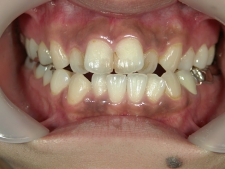

矯正歯科 治療前矯正歯科 治療前

30歳女性 浜松市北区在住

治療期間3年4ヶ月

主訴:前歯の歯並びが気になる。

矯正歯科 治療前 上顎を装置(QH)で拡大後ワイヤー矯正へ移行、右下5番左下4番 計2本抜歯叢生改善